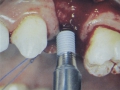

- 5.712 Implante para primeiro pré molar superior direito